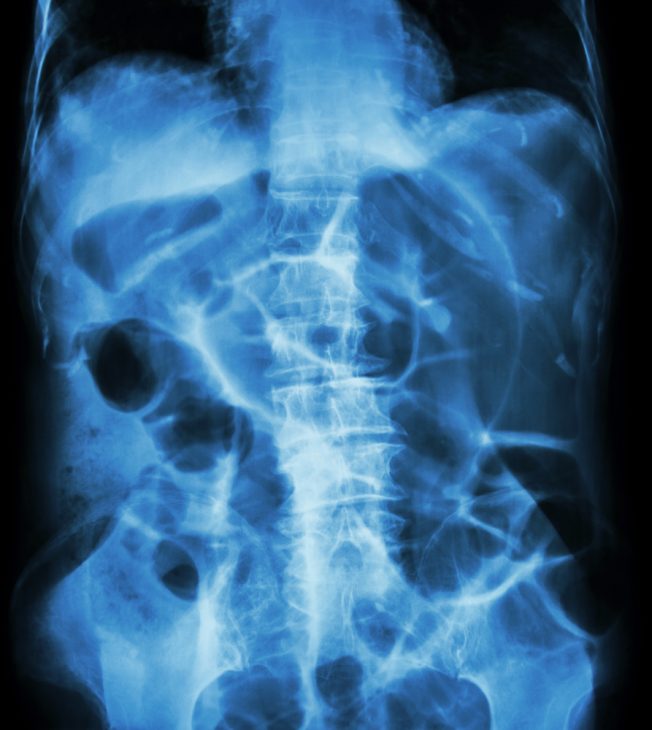

- Эталонным методом исследования является обзорная рентгенография органов брюшной полости в нескольких проекциях, так как при непроходимости кишечника на снимках в большинстве случаев обнаруживаются признаки, позволяющие точно установить диагноз.